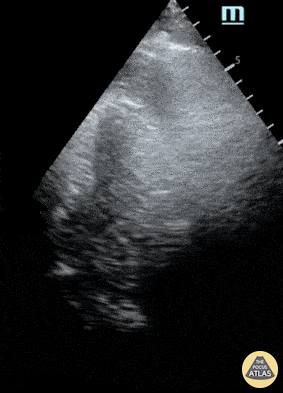

POCUS obtained during a cardiac arrest demonstrates both CPR in progress as well as a large pericardial effusion. This patient had been waiting for CT aortogram to further evaluate severe back pain prior to onset of arrest. The pericardial collection appears hyperechoic indicating clotted blood (most likely secondary to a Type A aortic dissection). An attempt at needle aspiration was unsuccessful and the patient died. Peter Cheng